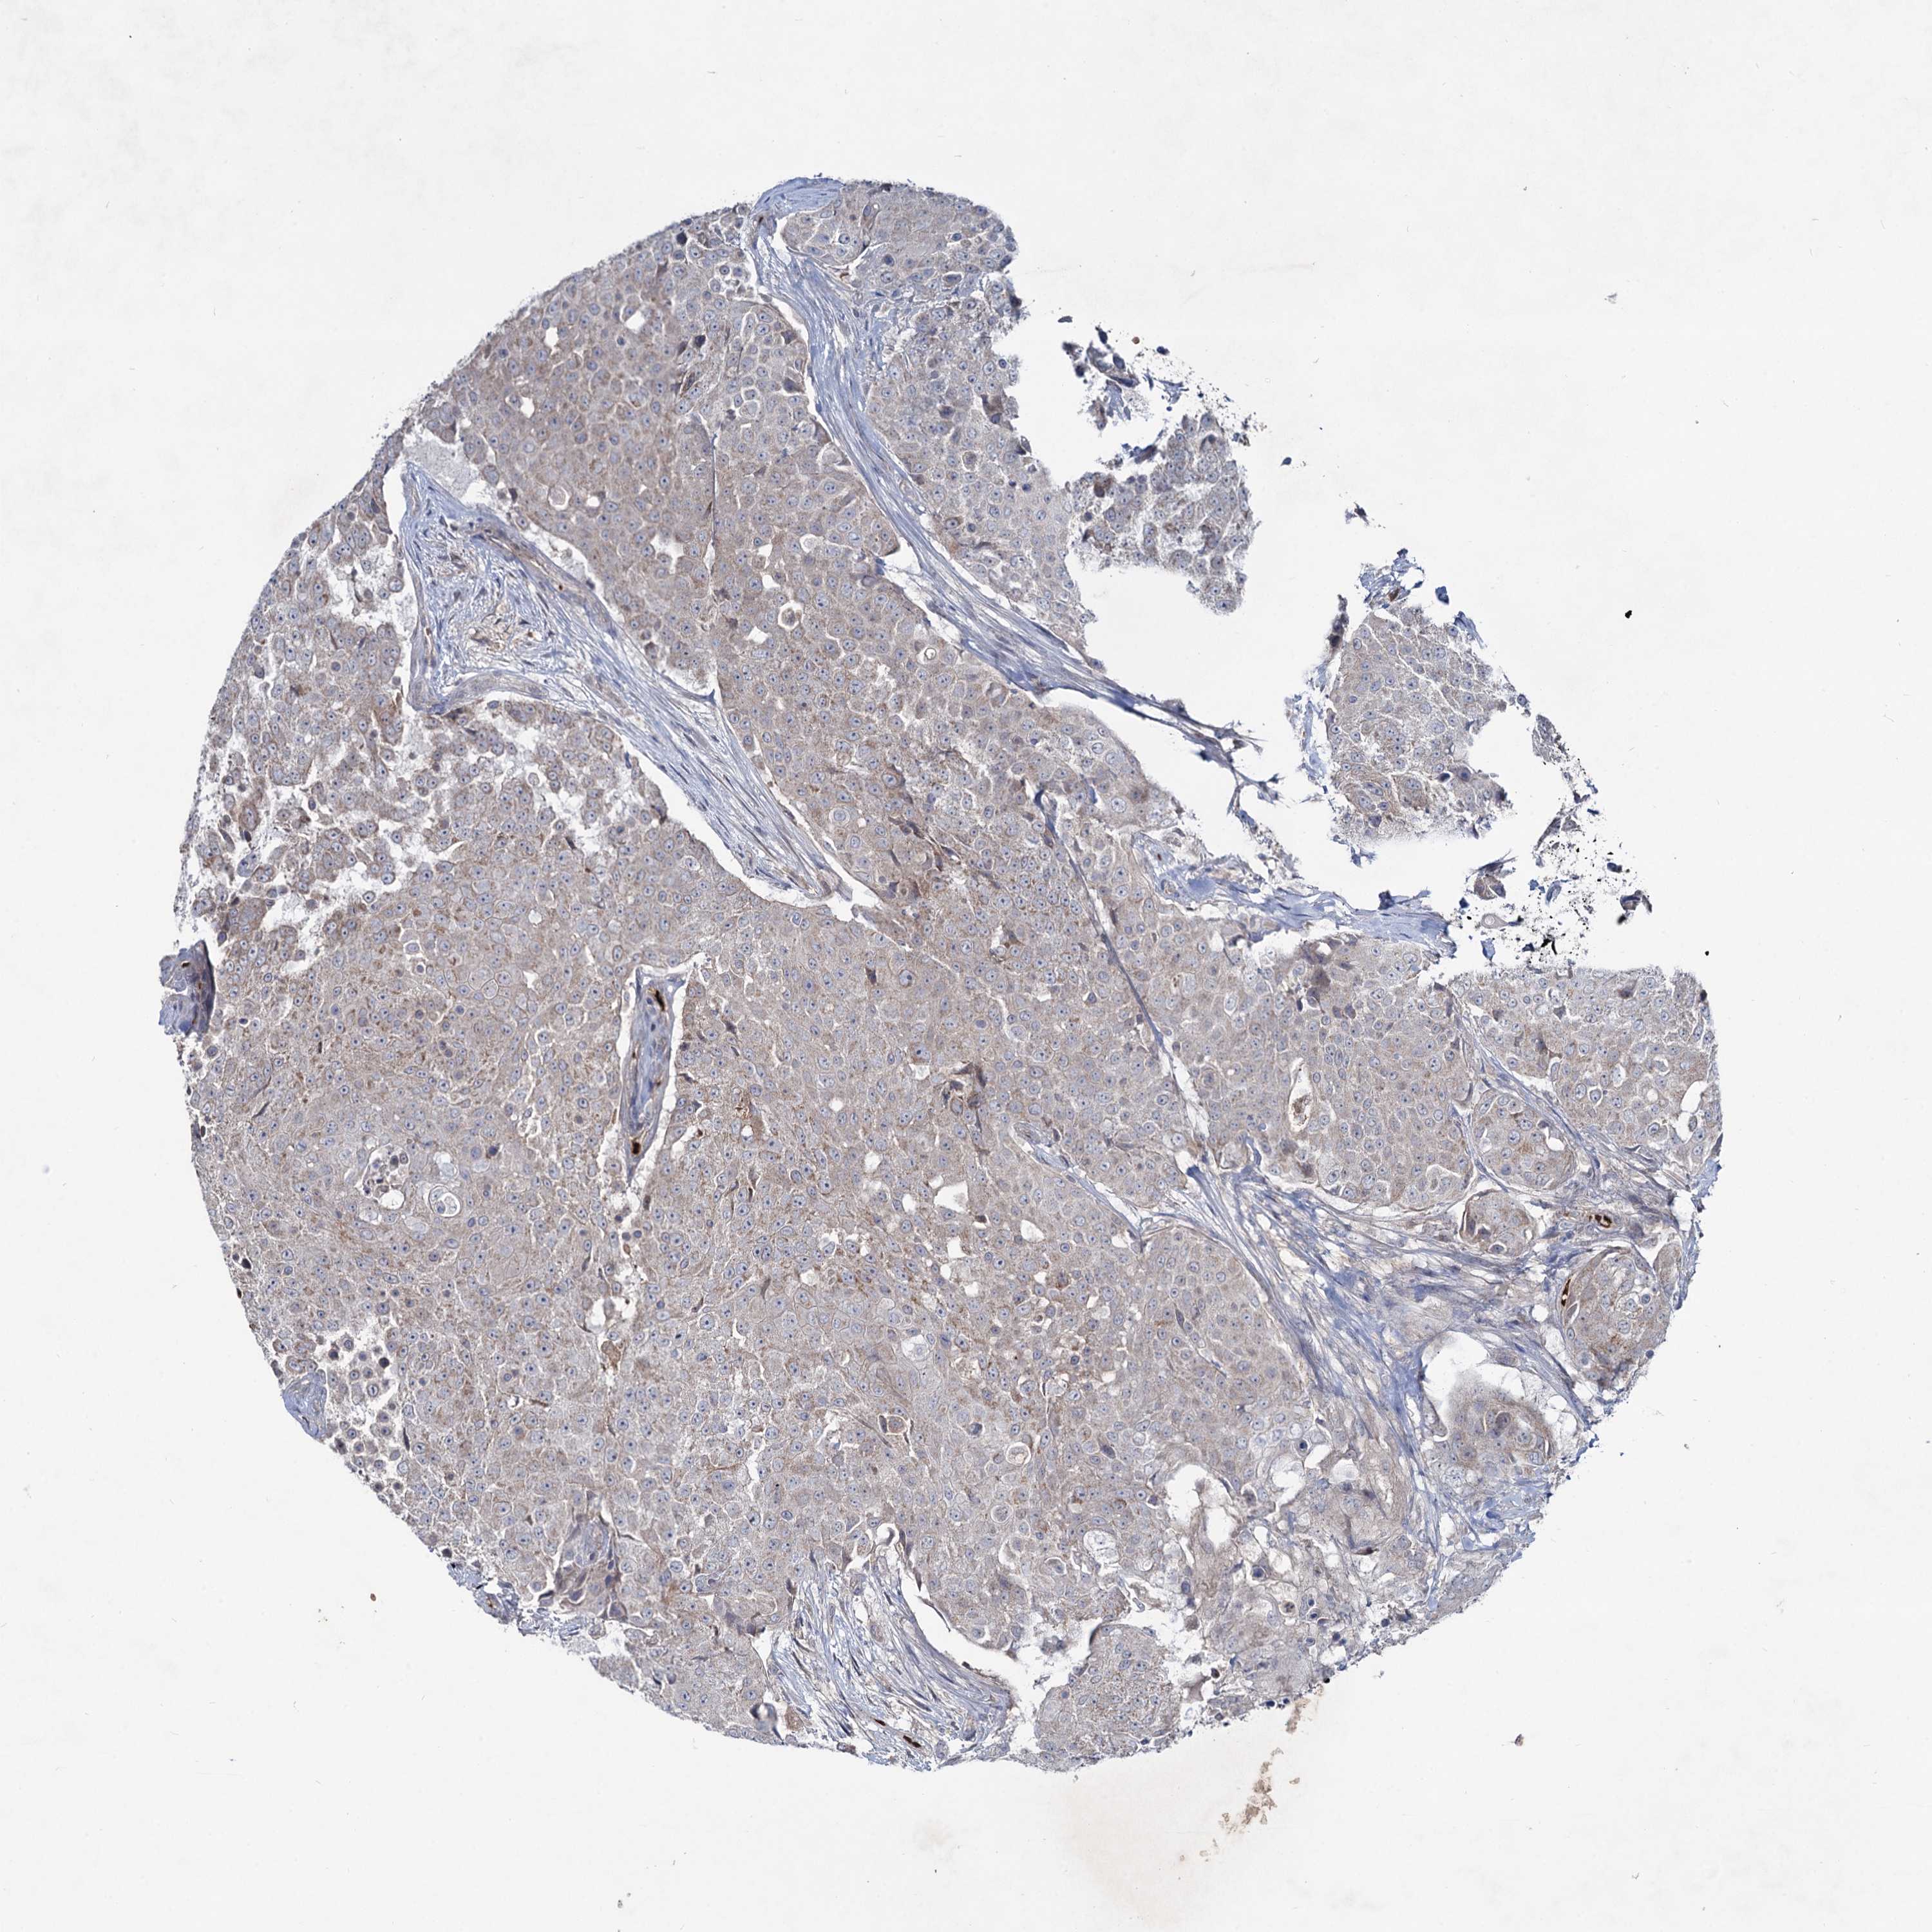

UROTHELIAL CANCER - Protein expressioni

A mouse-over function shows sample information and annotation data. Click on an image to view it in a full screen mode. Samples can be filtered based on level of antibody staining by selecting one or several of the following categories: high, medium, low and not detected. The assay and annotation is described here.

Note that samples used for immunohistochemistry by the Human Protein Atlas do not correspond to samples in the TCGA dataset.

Antibody stainingi

Antibody staining in the annotated cell types in the current human tissue is reported as not detected, low, medium, or high, based on conventional immunohistochemistry profiling in selected tissues. This score is based on the combination of the staining intensity and fraction of stained cells.

Each image is clickable and will lead to virtual microscopy that enables deeper exploration of all samples and also displays staining intensity scores, fraction scores and subcellular localization as well as patient and tissue information for each sample.

Antibody HPA039343

Antibody HPA040048

Urothelial carcinoma, High grade

Urothelial carcinoma, Low grade